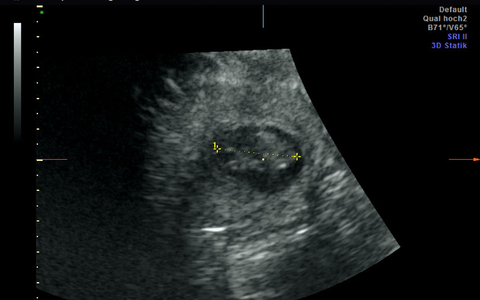

Wieder Panda-Nachwuchs im Berliner Zoo erwartet

TrÀchtig oder nicht? - Panda-Dame per Ultraschall untersucht. ...